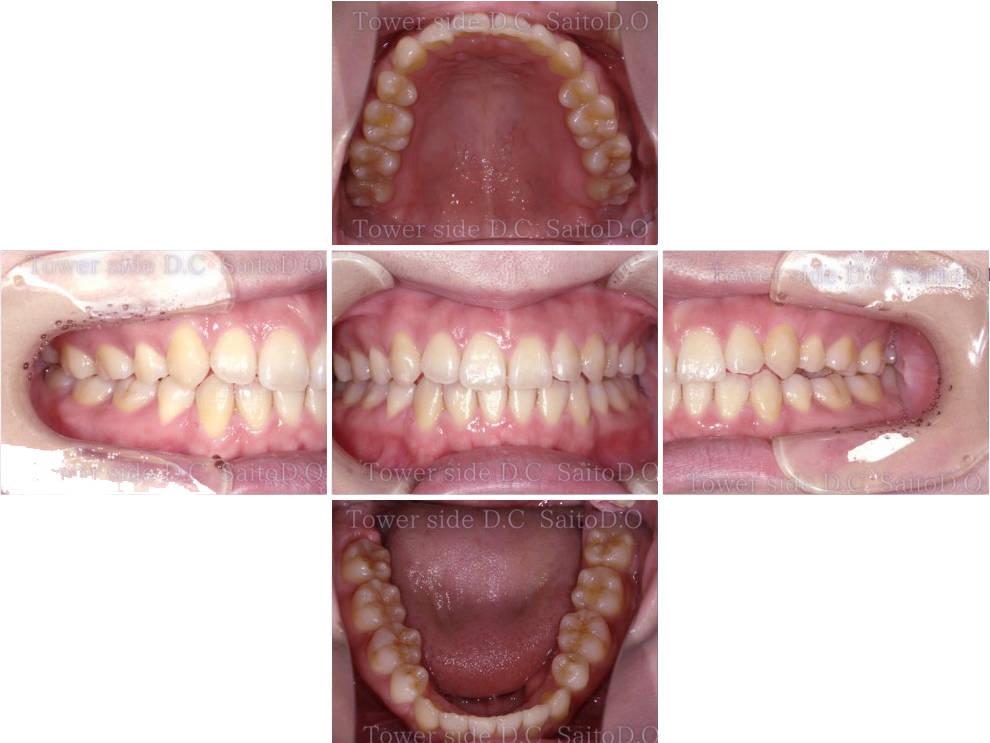

症例8CASE 8

|20代歳(女性)|

インビザラインエクスプレス

症例(施術前)

症例(施術後)

主訴 上顎側切歯の出っ張りを治したい

状況

• 上顎前歯叢生

• 上顎切歯口蓋側傾斜

• 下顎叢生

治療費 519,200円(税込)(自由診療)

治療期間 8ヶ月

治療内容 歯のディスキングを行い歯列を整えた。叢生は改善され、その後保定装置(リテーナー)を使用し安定している。

リスク

• 歯根呼吸や、歯根の成長が阻害される可能性、歯髄が壊死する可能性。

• 歯の痛み、顎の痛み、虫歯、歯周病、矯正器具により口腔粘膜の傷、喋りにくさが生じる可能性。

• 矯正治療後は、リテーナーを使用しないと歯の位置に後戻りが生じる可能性。